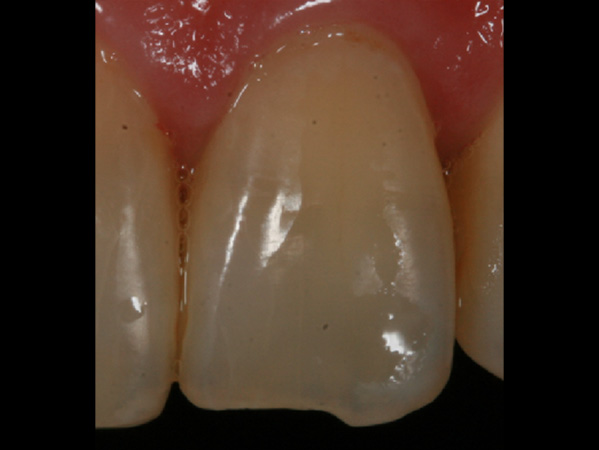

歯の表面に見られる白濁したシミのような斑点をホワイトスポットと呼びます。

初期う蝕はいわゆる穴のあいたう蝕の前段階のものです。歯の表面は溶けず、内側のミネラルなどが溶け出し空洞になることで光の屈折率が変わりホワイトスポットとして見た目に影響が出ます。

エナメル質形成不全ではう蝕とは異なり内部が空洞化することはありませんが、内部の構造が乱れることで光の屈折率が変わり、ホワイトスポットとして審美的に問題を生じます。